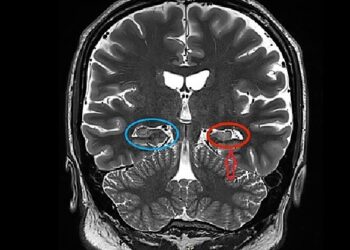

What makes up the cell’s “brain”?

Nucleus

Like the cell’s mind, the nucleus functions as the cell. It aids in the regulation of eating, movement, and reproduction. The nucleus probably knows about it if it occurs in a cell.